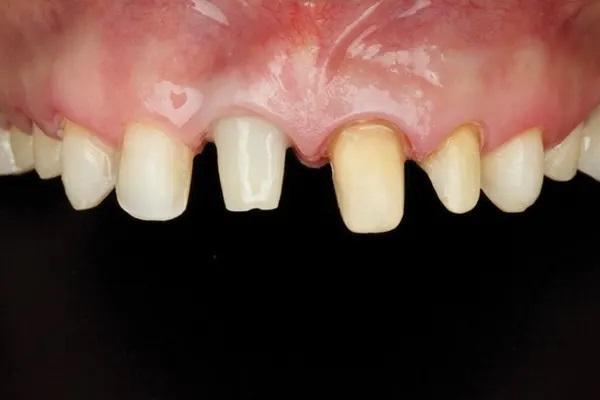

Пациентка 33 лет обратилась с жалобами на дефект прямой реставрации в переднем отделе выполненной из специальной смолы, имеющаяся у нее конструкция с опорой на имплантаты также имела дефект, а именно скол керамики по режущему краю резца и соседние зубы аномального размера (Фото 1 - Фото 3). В ее истории болезни не было выявлено противопоказаний к стоматологическому лечению. В 2015 году для восстановления целостности зубного ряда ей был установлен имплантат в области зуба 1.1., и рентгенологическое исследование показало, что имплантат хорошо сросся с костью. Глубина зондирования пародонта и тканей, окружающих имплантат, составляла от 3 до 4 мм, без признаков активного воспаления. У пациентки был хороший уровень гигиены полости рта.

Фото 3. Внутриротовое фото зубов верхней челюсти до начала лечения.